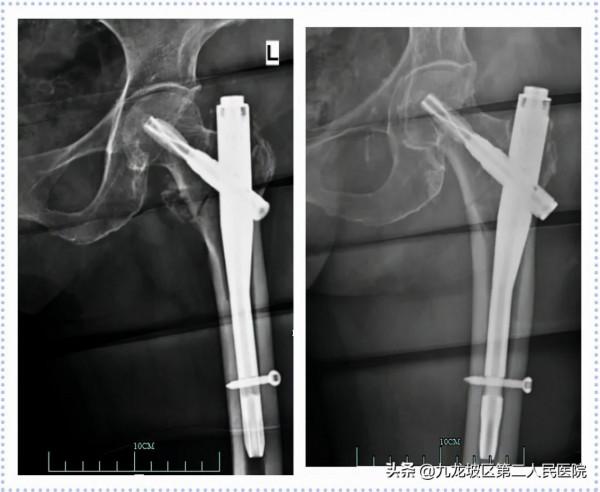

82歲女性,因“不慎跌倒致左髖部疼痛伴活動受限1天”入院。診斷為“左股骨粗隆間粉碎性骨折(EvansⅠd型)”。2020年12月14日在我院骨科行左股骨粗隆間骨折閉合復位髓內針內固定術(PFNA)。

56歲男性,因“車禍致左髖部疼痛伴功能障礙2+小時”入院。診斷為“左股骨粗隆間粉碎性骨折(EvansⅠd型)”。2021年06月02日在我院骨科行左股骨粗隆間骨折閉合復位內固定術(InterTan)。